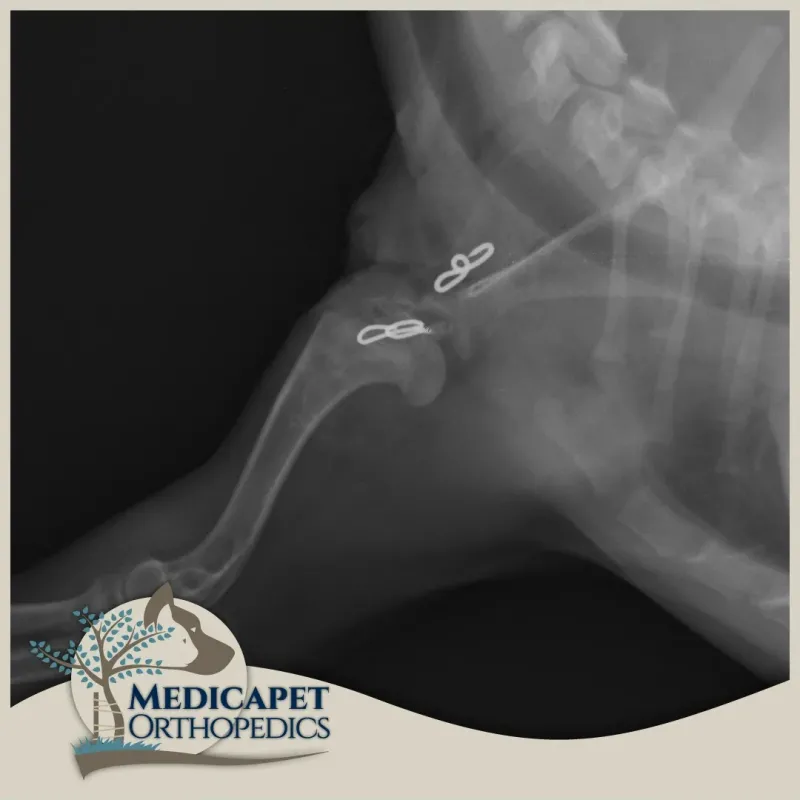

Omuz instabilitesinin tedavisi, burkulma ve zorlanma derecesine ve instabilite derecesine bağlıdır. Düşük dereceli yaralanmalar genellikle anti-inflamatuar ilaçlar, egzersiz modifikasyonu, fizyoterapi ve hidroterapi ile cerrahi olmayan bir şekilde tedavi edilir. Yüksek dereceli yaralanmalar ise stabilizasyon, omuz füzyonu veya total omuz replasmanı kullanılarak tedavi edilebilir.

omuz-instabilitesi-2